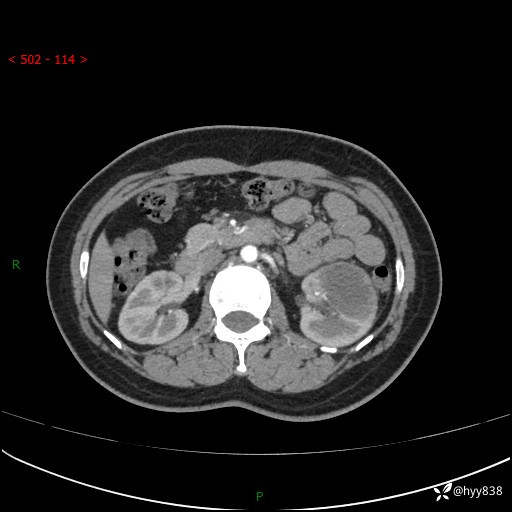

现病史:患者于1周前因左侧腰腹部间断胀痛不适,无恶心呕吐,无明显肉眼血尿,无畏寒发热,无尿频尿急,起病初,患者来我院就诊,查CT提示左肾低密度影,外周血提示:白细胞11.25*10^9/L.行抗感染治疗后未见明显好转,06-18泌尿系增强CT提示左肾类圆形低密度占位(脓肿?肿瘤?),大小:4.0*3.2cm,为求进一步治疗,门诊以“左肾占位”收住我科。 起病以来,患者精神佳,饮食、睡眠良好,大小便正常,体力体重无明显变化。

双肾CT平扫+增强